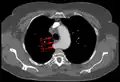

Computed Tomography (CT) Angiography: CT scans with contrast provide high-resolution, 3D images of blood vessels, allowing clear visualization of the ASA’s location and course relative to the trachea and esophagus.